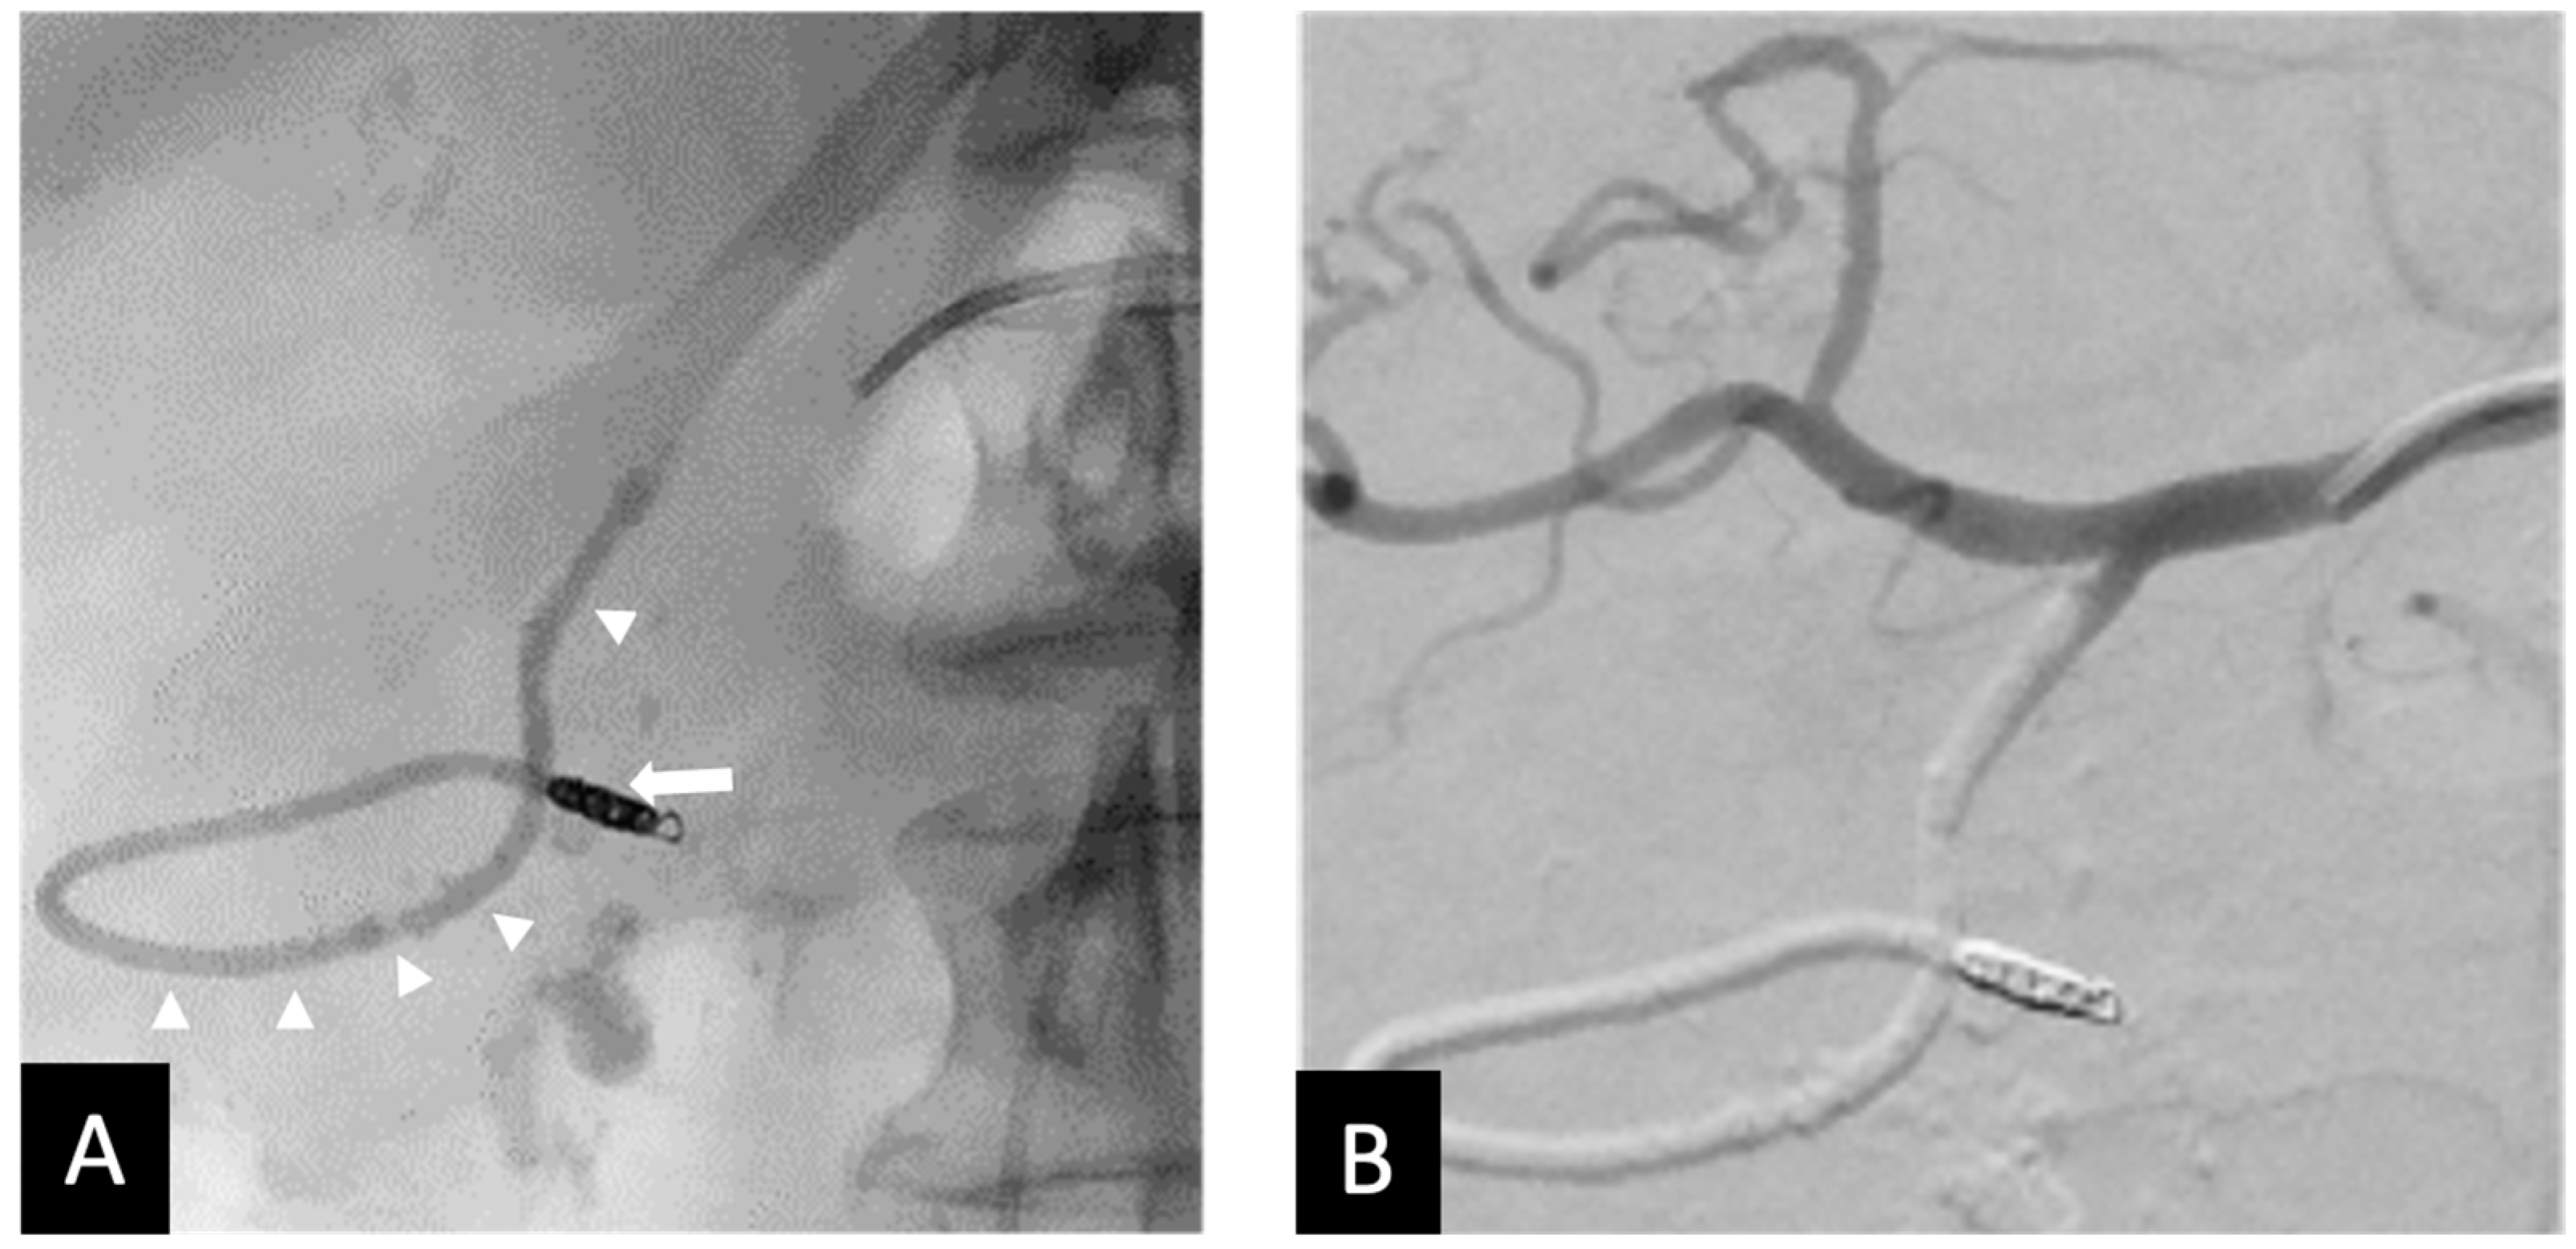

Figure 4. Fifty-five y.o male with bleeding duodenal ulcer. (A) Ta-OCE embolization of the GDA without using a backstop coil in distal GDA/proximal RGEA. (Arrow shows extension of Ta-OCE in the mid- to distal RGEA). (B) Post-GDA embolization DSA, demonstrating adequate GDA embolization and better visualization of Ta-OCE cast in the mid- and distal RGAE (arrow). (C) CT scan showing Ta-OCE extension into the distal RGEA post-embolization (arrow). Bleeding was successfully treated in this patient with no sign of bowel ischemia or injury. Image obtained from patient’s chart. Source: NK.